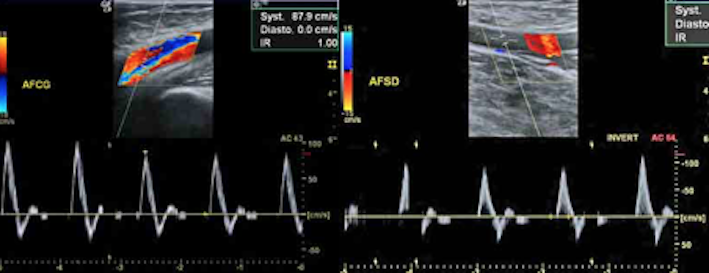

- les troncs supra-aortiques (artères cervicales) : recherche et suivre un athérome,une sténose, une dissection

- le transcrânien :apprécie la circulation des artères intracrâniennes, est généralement couplé à l’examen des troncs supra-aortiques